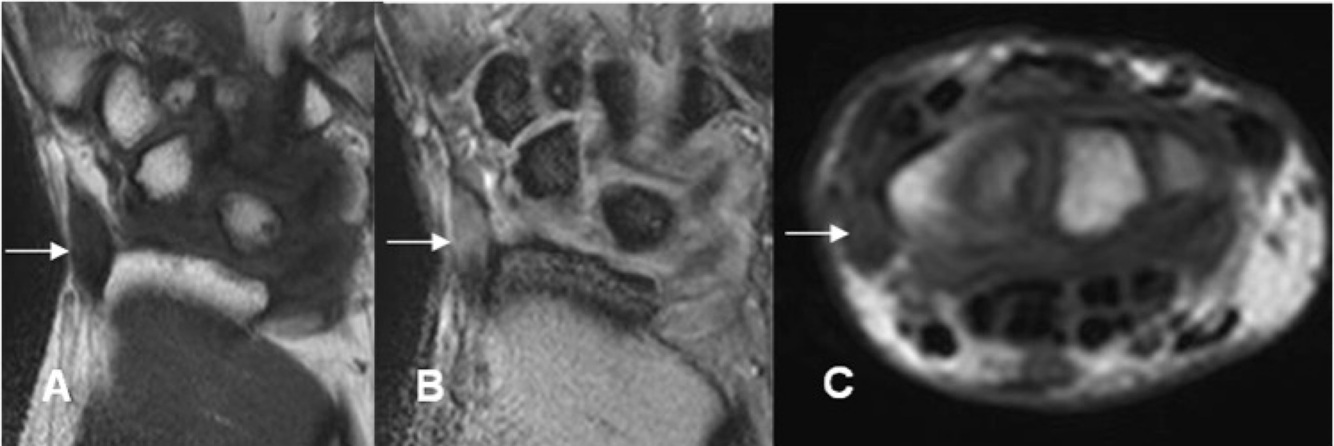

RM Tenosinovitis de quervain

Hiperintensidad T2 tendon

Edema subcutáneo peritendinoso

Captación del contraste